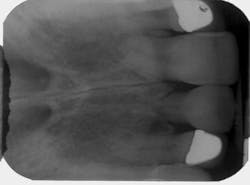

Initial examination of the patient included comprehensive periodontal and restorative examinations and charting; full-mouth radiographs; and evaluation of the smile line, occlusion, hard- and soft-tissue architecture, and interdental/interarch space. The site of the mobile central incisor was found to be free of any pathology. Radiographic examination revealed that the root of Tooth No. 9 was severely resorbed (Figure 2), and the tooth's long-term prognosis was judged to be poor. A decision was made to have the mobile central incisor extracted and immediately replaced with an implant. Immediate placement has been demonstrated to help preserve the hard- and soft-tissue architecture.3,4